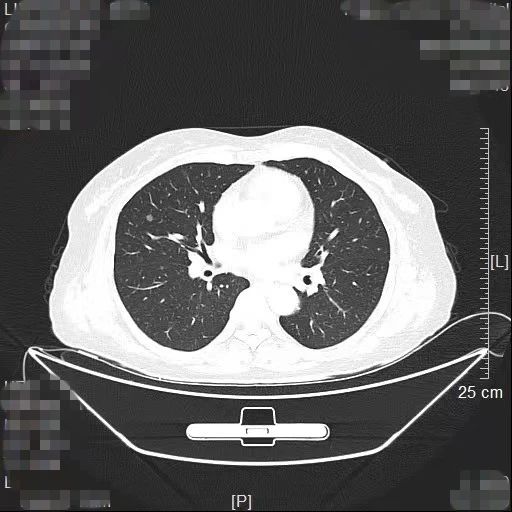

近日,我院胸部肿瘤外科方卫民主任医师团队通过“针孔消融+单孔微创”的杂交手术,为患者同时解除2个高危肺结节,手术切口仅为一个针眼加一个3cm的微创切口。